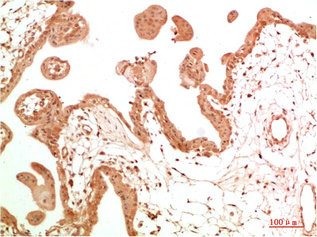

• Immunohistochemical analysis of paraffin-embedded Human Skin Tissue using c-Abl Rabbit pAb diluted at 1:200